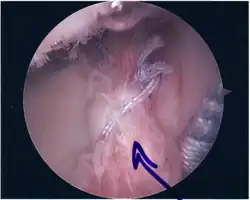

Repair of SLAP Tear

Arthroscopic SLAP Lesion (type 2) repair

Following inspection and determination of the extent of injury, the basic labrum repair is as follows.

• The glenoid and labrum are roughened to increase contact surface area and promote re-growth.

• Locations for the bone anchors are selected based on number and severity of tear. A severe tear involving both SLAP and Bankart lesions may require seven anchors. Simple tears may only require one.

• The glenoid is drilled for the anchor implantation.

• Anchors are inserted in the glenoid.

• The suture component of the implant is tied through the labrum and knotted such that the labrum is in tight contact with the glenoid surface.